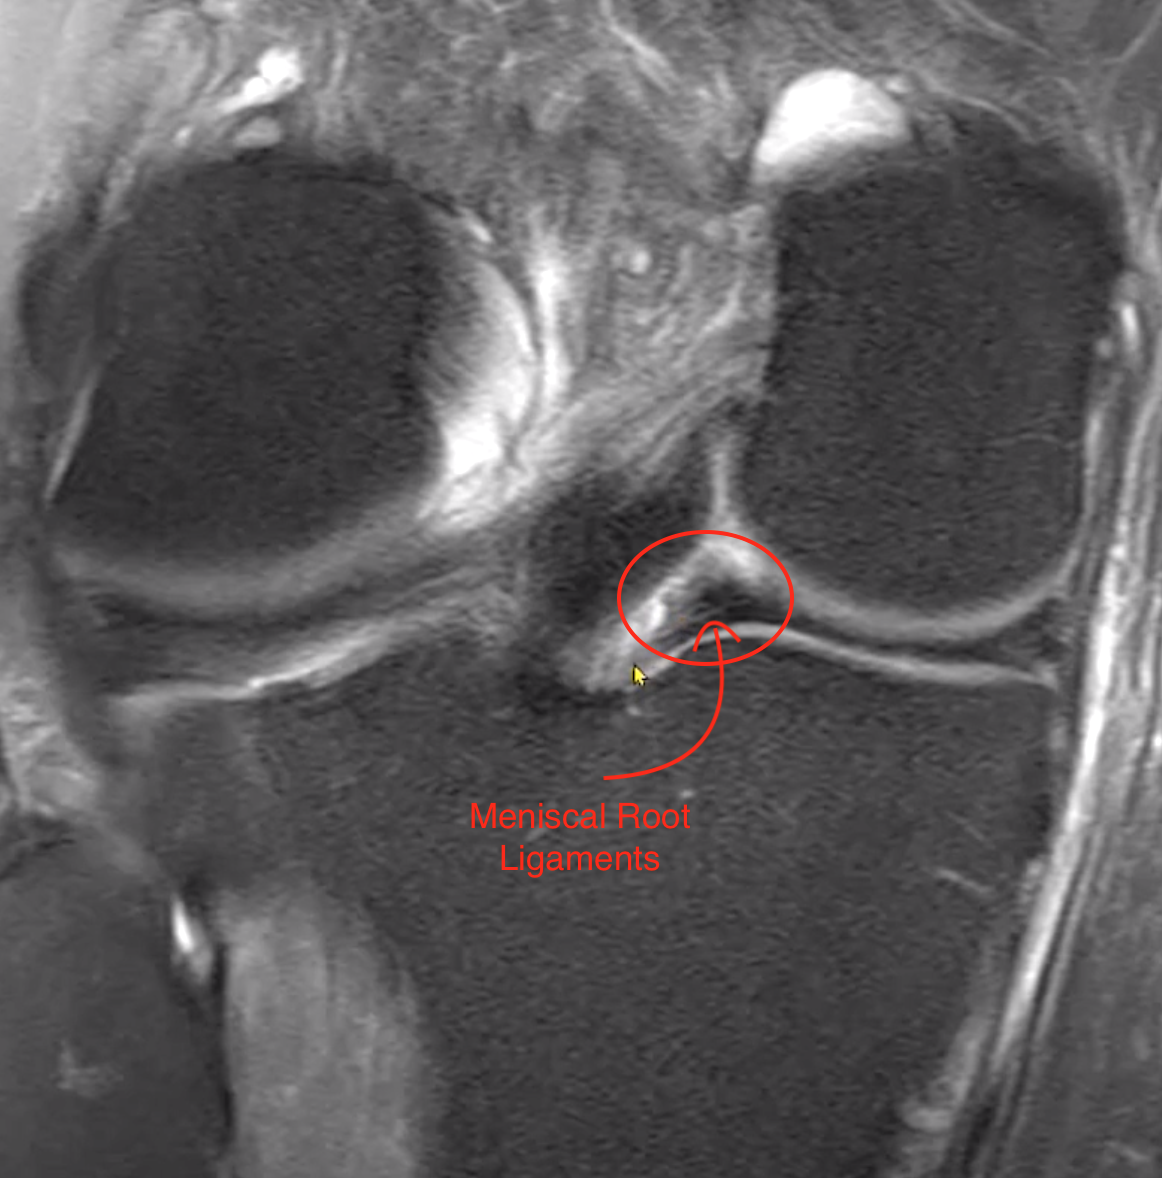

• Meniscal root ligaments

• Attach on anterior aspect of meniscus

• Attach on posterior aspect of meniscus

• Injury/tear of root ligaments can be from 3 major causes

• Destruction of the ligaments themselves

• Destruction of the medial tip of the meniscus where they attach

• Destruction of underlying bone which basically avulses

• When this happens the meniscus medial attachment will be lost and will allow the meniscus to sway medial and laterally which can result in protrusion

• Additionally the recurrent sway medial and lateral causes a horizontal fissure within the meniscus which may they extend to the medial border where the original injury to the root ligament started